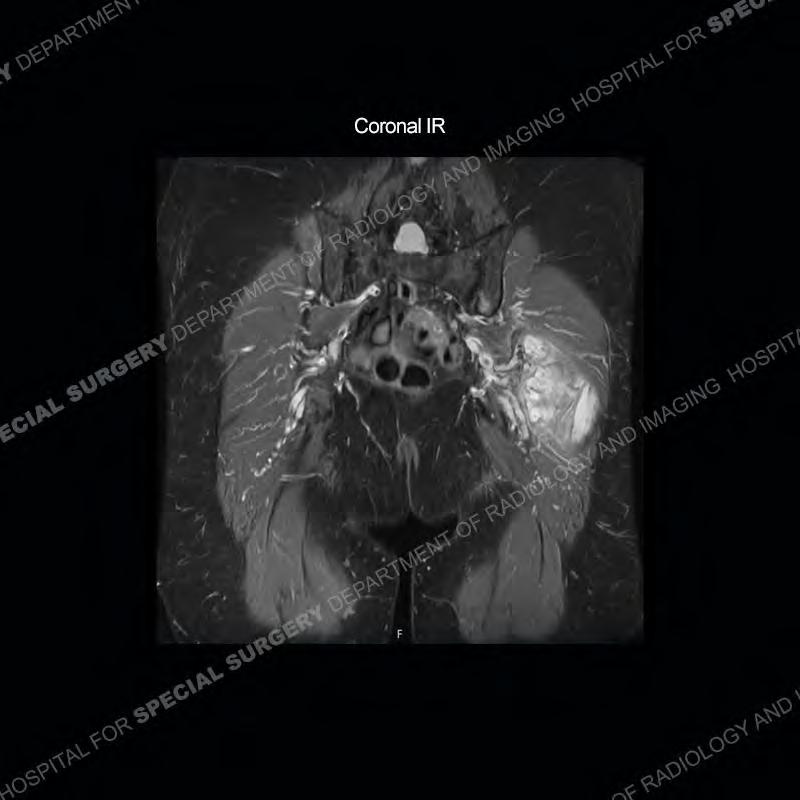

The radiograph is not particularly contributory in this case. The MRI demonstrates markedly abnormal architecture of the gluteus minimus and anterolateral band of the gluteus medius. Portions of the tendons are high signal, portions are highly attenuated, and portions are disrupted. A large, complex fluid collection is present in the adjacent soft tissue.

Diagnosis: Gluteal Tendinosis and Disruption with Complex Trochanteric Bursal Collection

Not as much of a diagnostic dilemma as many of the other cases shown but just a nice example of the pathology seen of the gluteal tendons and a cause of trochanteric pain. Although, frequently thought of in isolation, trochanteric bursitis or bursal thickening is much more commonly a reactive change to underlying pathology of the subjacent gluteal tendons. The gluteus medius is divided into a posterior band and an anterolateral band. Tendinosis and partial tearing very commonly will involve the gluteus minimus and especially the more posterior fibers and then propagate into the anterior lateral band of the gluteus medius. Involvement of the posterior band of the medius is much less common and engenders a marked degree of functional impairment.

The bursae about the greater trochanter can be a little bit confusing especially given the terminology. Trochanteric bursitis is implied to mean the subgluteus maximus bursa which is present deep to the maximus and just lateral/superficial to the trochanter. That is the bursa involved in this case. In this case the complexity of the bursa relates to the tendon tearing with inflammatory change and probably hemorrhage accounting for the complexity. Two other, less frequently involved bursa are also present. The subgluteus medius and subgluteus minimus bursa are found just deep to the named tendons. Although pathology does frequently follow the previously described pattern it is possible to have isolated pathology to either the medius or minimus.